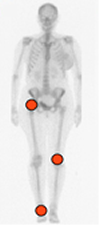

Los pacientes generalmente consultan por dolor, eritema, edema y limitación funcional. En el Dx diferencial de una monoartropatía aguda, se debe considerar la artritis séptica y la artropatía por cristales, como principales causas. (16). (Fig 60).

Fig 60. Distribución de la artropatía infecciosa.

Afección monoarticular, de las articulaciones grandes de la extremidad inferior.